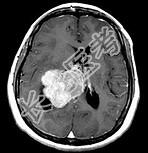

- 单项选择题女,45岁, 右眼视力下降8个月,右颜面麻木半个月, 时有头昏,味觉减退, 请根据所提供图像,选择最可能的诊断是 ( )

A、(右侧脑室)胶质瘤

B、(右侧脑室)脉络膜乳头状瘤

C、(右侧脑室)转移瘤

D、(右侧脑室)室管膜瘤

E、(右侧脑室)脑膜瘤(合体细胞型)